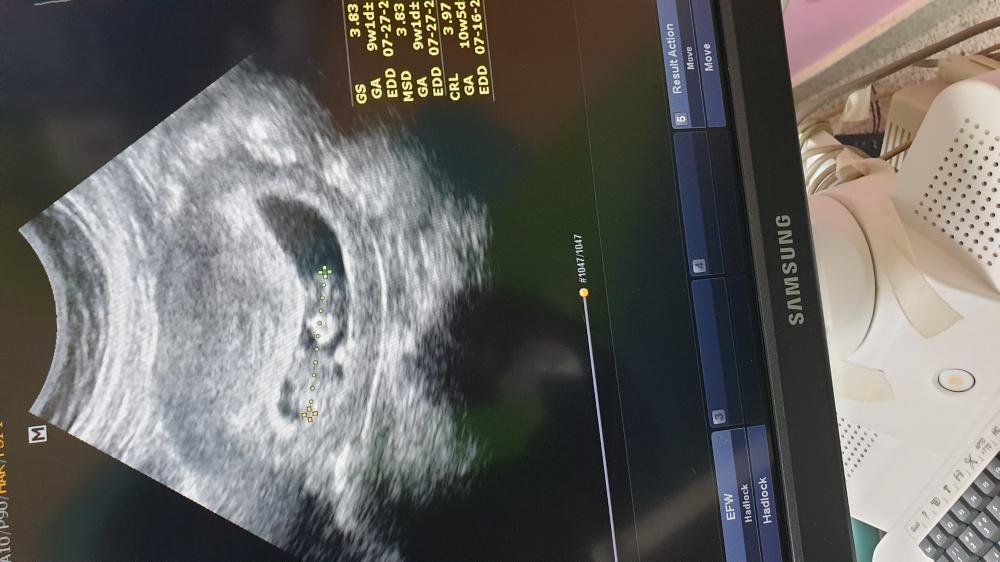

ام سطام انا مثلك نفس وضعك ومرا خايفة حملي اللي قبل كانت المشيمة لازقة بالجرح الاول والحين رحت موعدي قبل كم يوم قالت نفس وضع حملك اللي قبل بيتكرر لان المشيمة نازلة ومقفلة عنق الرحم طبعاً قد جاني نزيف مرتين واخذ مثبتات واسبرين وخايفة يستأصلون الرحم عندي 😭😭 عشان كذا خاطري بالولد مرا مرا 🥺